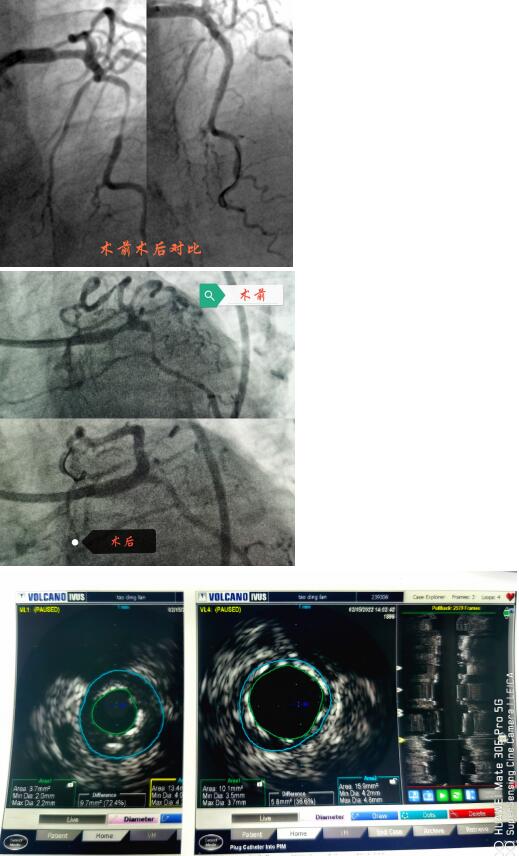

春節(jié)剛過(guò),陶奶奶的孩子們帶著陶奶奶再次來(lái)到了江寧中醫(yī)院心內(nèi)科準(zhǔn)備拆除這顆潛在的“致命炸彈”。韋鋒主任反復(fù)研究陶奶奶的前期手術(shù)影像,心中擬定著多個(gè)手術(shù)方案。經(jīng)過(guò)充分準(zhǔn)備,2月15日,韋鋒主任再次為陶奶奶進(jìn)行了介入手術(shù)。術(shù)中通過(guò)血管內(nèi)超聲(IVUS)精細(xì)、準(zhǔn)確評(píng)估陶奶奶的冠脈病變情況,發(fā)現(xiàn)陶奶奶的左主干最小管腔面積僅僅3.7mm2,;前降支近段全程鈣化,最嚴(yán)重處呈270度的環(huán)形鈣化,最小管腔面積僅僅2.1mm2;回旋支開(kāi)口正常,回旋支近端最小管腔面積1.8mm2。韋鋒主任根據(jù)IVUS的結(jié)果,改變了原來(lái)擬定的DKCRUSH術(shù)式,決定采用藥物球囊和藥物涂層支架相結(jié)合的方式處理病變(LCX藥物球囊,LM-LAD植入支架),經(jīng)過(guò)近2個(gè)小時(shí)的手術(shù),陶奶奶的冠脈血管又“完美”地回來(lái)了。

韋鋒主任術(shù)中在仔細(xì)研究陶奶奶的IVUS結(jié)果,指導(dǎo)手術(shù)更精確的進(jìn)行。

據(jù)韋鋒主任介紹,上世紀(jì)八十年代,類(lèi)似陶奶奶的這種累及左主干的多支病變,曾被視為內(nèi)科微創(chuàng)介入的禁忌,隨著心內(nèi)科微創(chuàng)介入技術(shù)的發(fā)展和支架的更新?lián)Q代,目前,這類(lèi)病變可以在有豐富介入經(jīng)驗(yàn)的介入醫(yī)生面前“迎刃而解”,不再是那么的可怕。近幾年隨著IVUS、OCT等腔內(nèi)影像學(xué)的發(fā)展,這類(lèi)病變可以更精準(zhǔn)的進(jìn)行治療。比如陶奶奶這個(gè)情況,在IVUS指導(dǎo)下,可以精確測(cè)量左主干的狹窄程度和長(zhǎng)度,指導(dǎo)支架的選擇;準(zhǔn)確評(píng)價(jià)左主干的解剖形態(tài)及病變性質(zhì),結(jié)合分叉處各分支開(kāi)口的病變情況,制定更優(yōu)更個(gè)體化的介入治療策略,并且評(píng)價(jià)支架置入后的效果優(yōu)化支架置入的過(guò)程,整體改善患者遠(yuǎn)期預(yù)后。